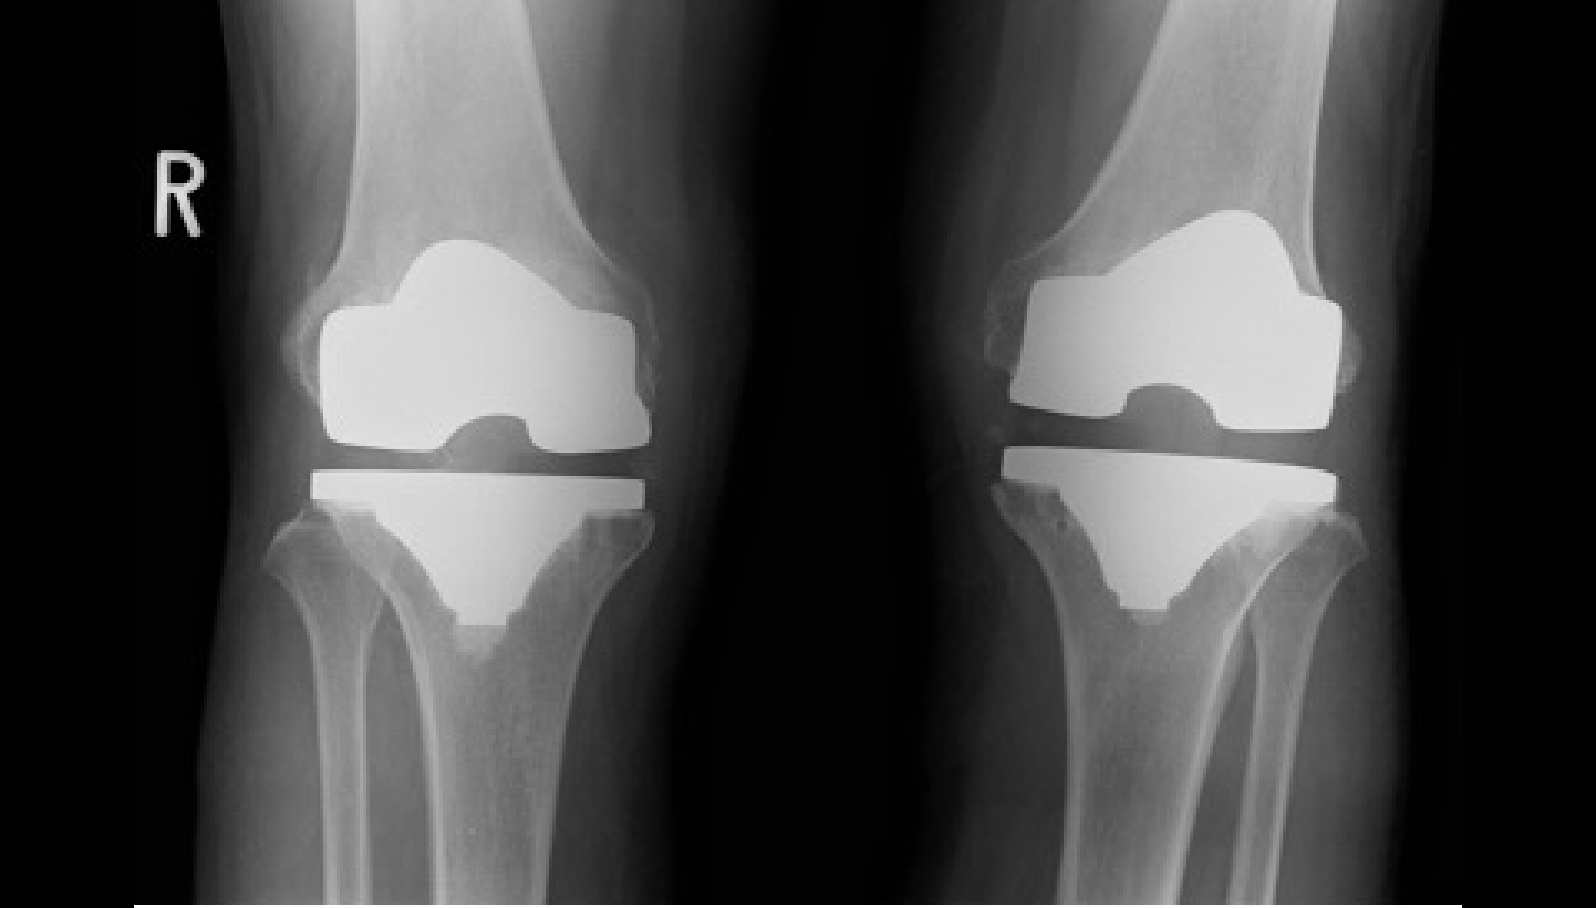

手術前後レントゲン画像

単顆型人工膝関節置換術

術後